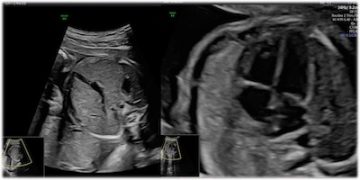

How To Do Giugno 2024: diagnosi e gestione delle anemie fetali

Cari soci, questo mese un nuovo video "How to do", dedicato alla diagnosi e alla gestione delle anemie fetali. Grazie a Tiziana Fanelli! Il video è accessibile ai soli soci...